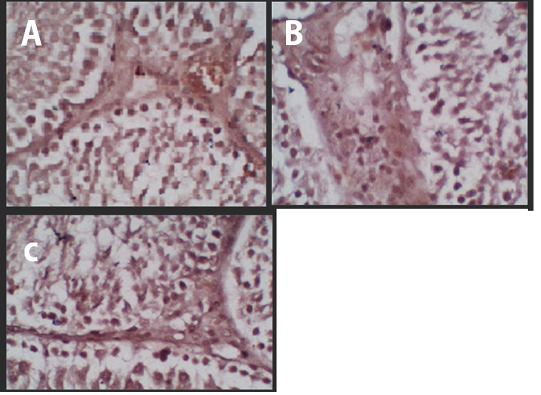

Figure 1

Immunohistochemistry of the p53 Protein Expression. (A) Negative Control, (B) Treatment 1 (T1) with Cepoka eggplant extract, (C) Treatment 2 (T2) with Kapok seed extract.